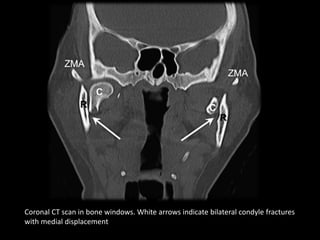

Coronal CT scan in bone windows. White arrows indicate bilateral condyle fractures

with medial displacement